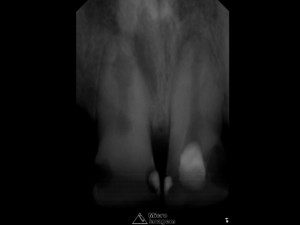

Paciente do gênero masculino, 32 anos, apresentou-se com quadro clínico de necrose pulpar dos elementos dentais 11 e 12 (figura 1), associado à presença de reabsorção interna, sendo submetido ao tratamento endodôntico em ambos os elementos.

- Figura 1